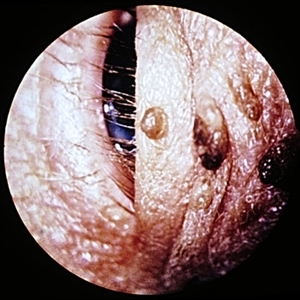

Slide 5-11 Slide 5-11Feb 20 2019 by Lancaster Course in Ophthalmology Molluscum contagiosum nodule on lid margin. Condition/keywords: eye lid, molluscum contagiosum nodule